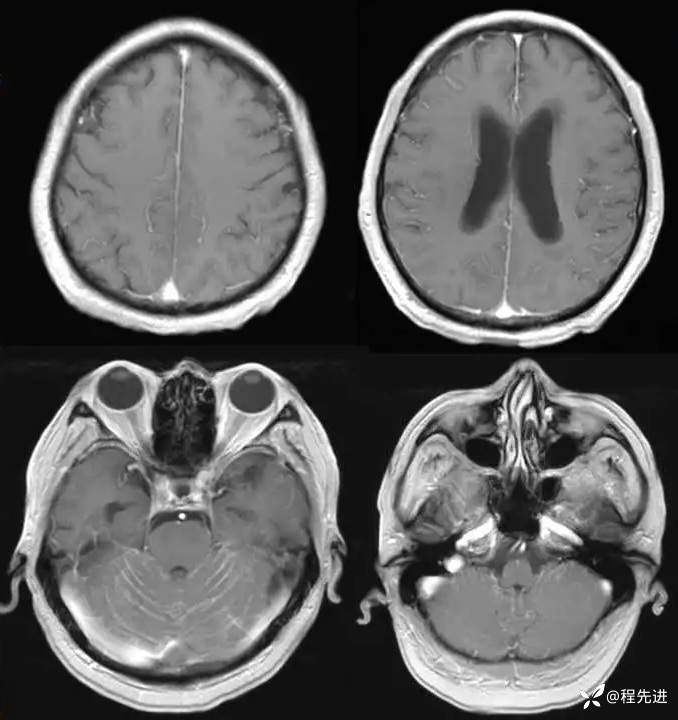

MR平扫+增强: